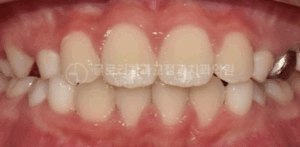

중랑구 교정치과 인비절라인 퍼스트, 우리 아이 삐뚤빼뚤한 치아도 어린이교정으로 개선될 수 있을까요?

안녕하세요, 중랑구 교정치과 김정은 원장입니다. 25.01.25 아이의 치아가 고르지 않거나 돌출입이 관찰되기 시작하면 '교정치료를 언제 시작해야될까' 하는 걱정과 함께 부모님 마음이 조급해지실 수 있습니다. 영구치가 다 나올 때까지 기다려야 하는지,…